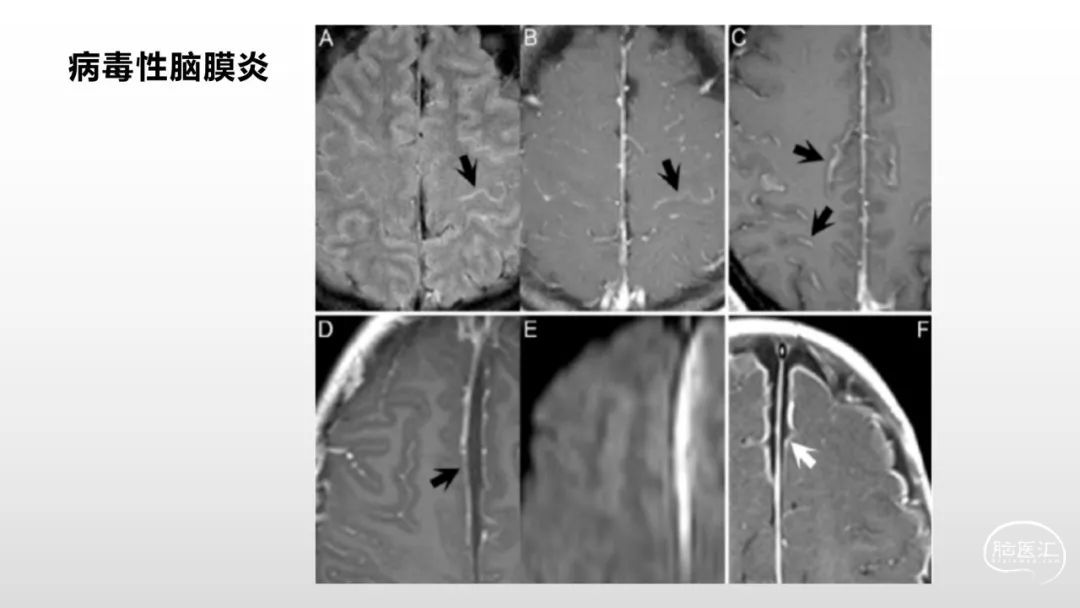

颅脑影像诊断基础知识讲座:脑膜病变